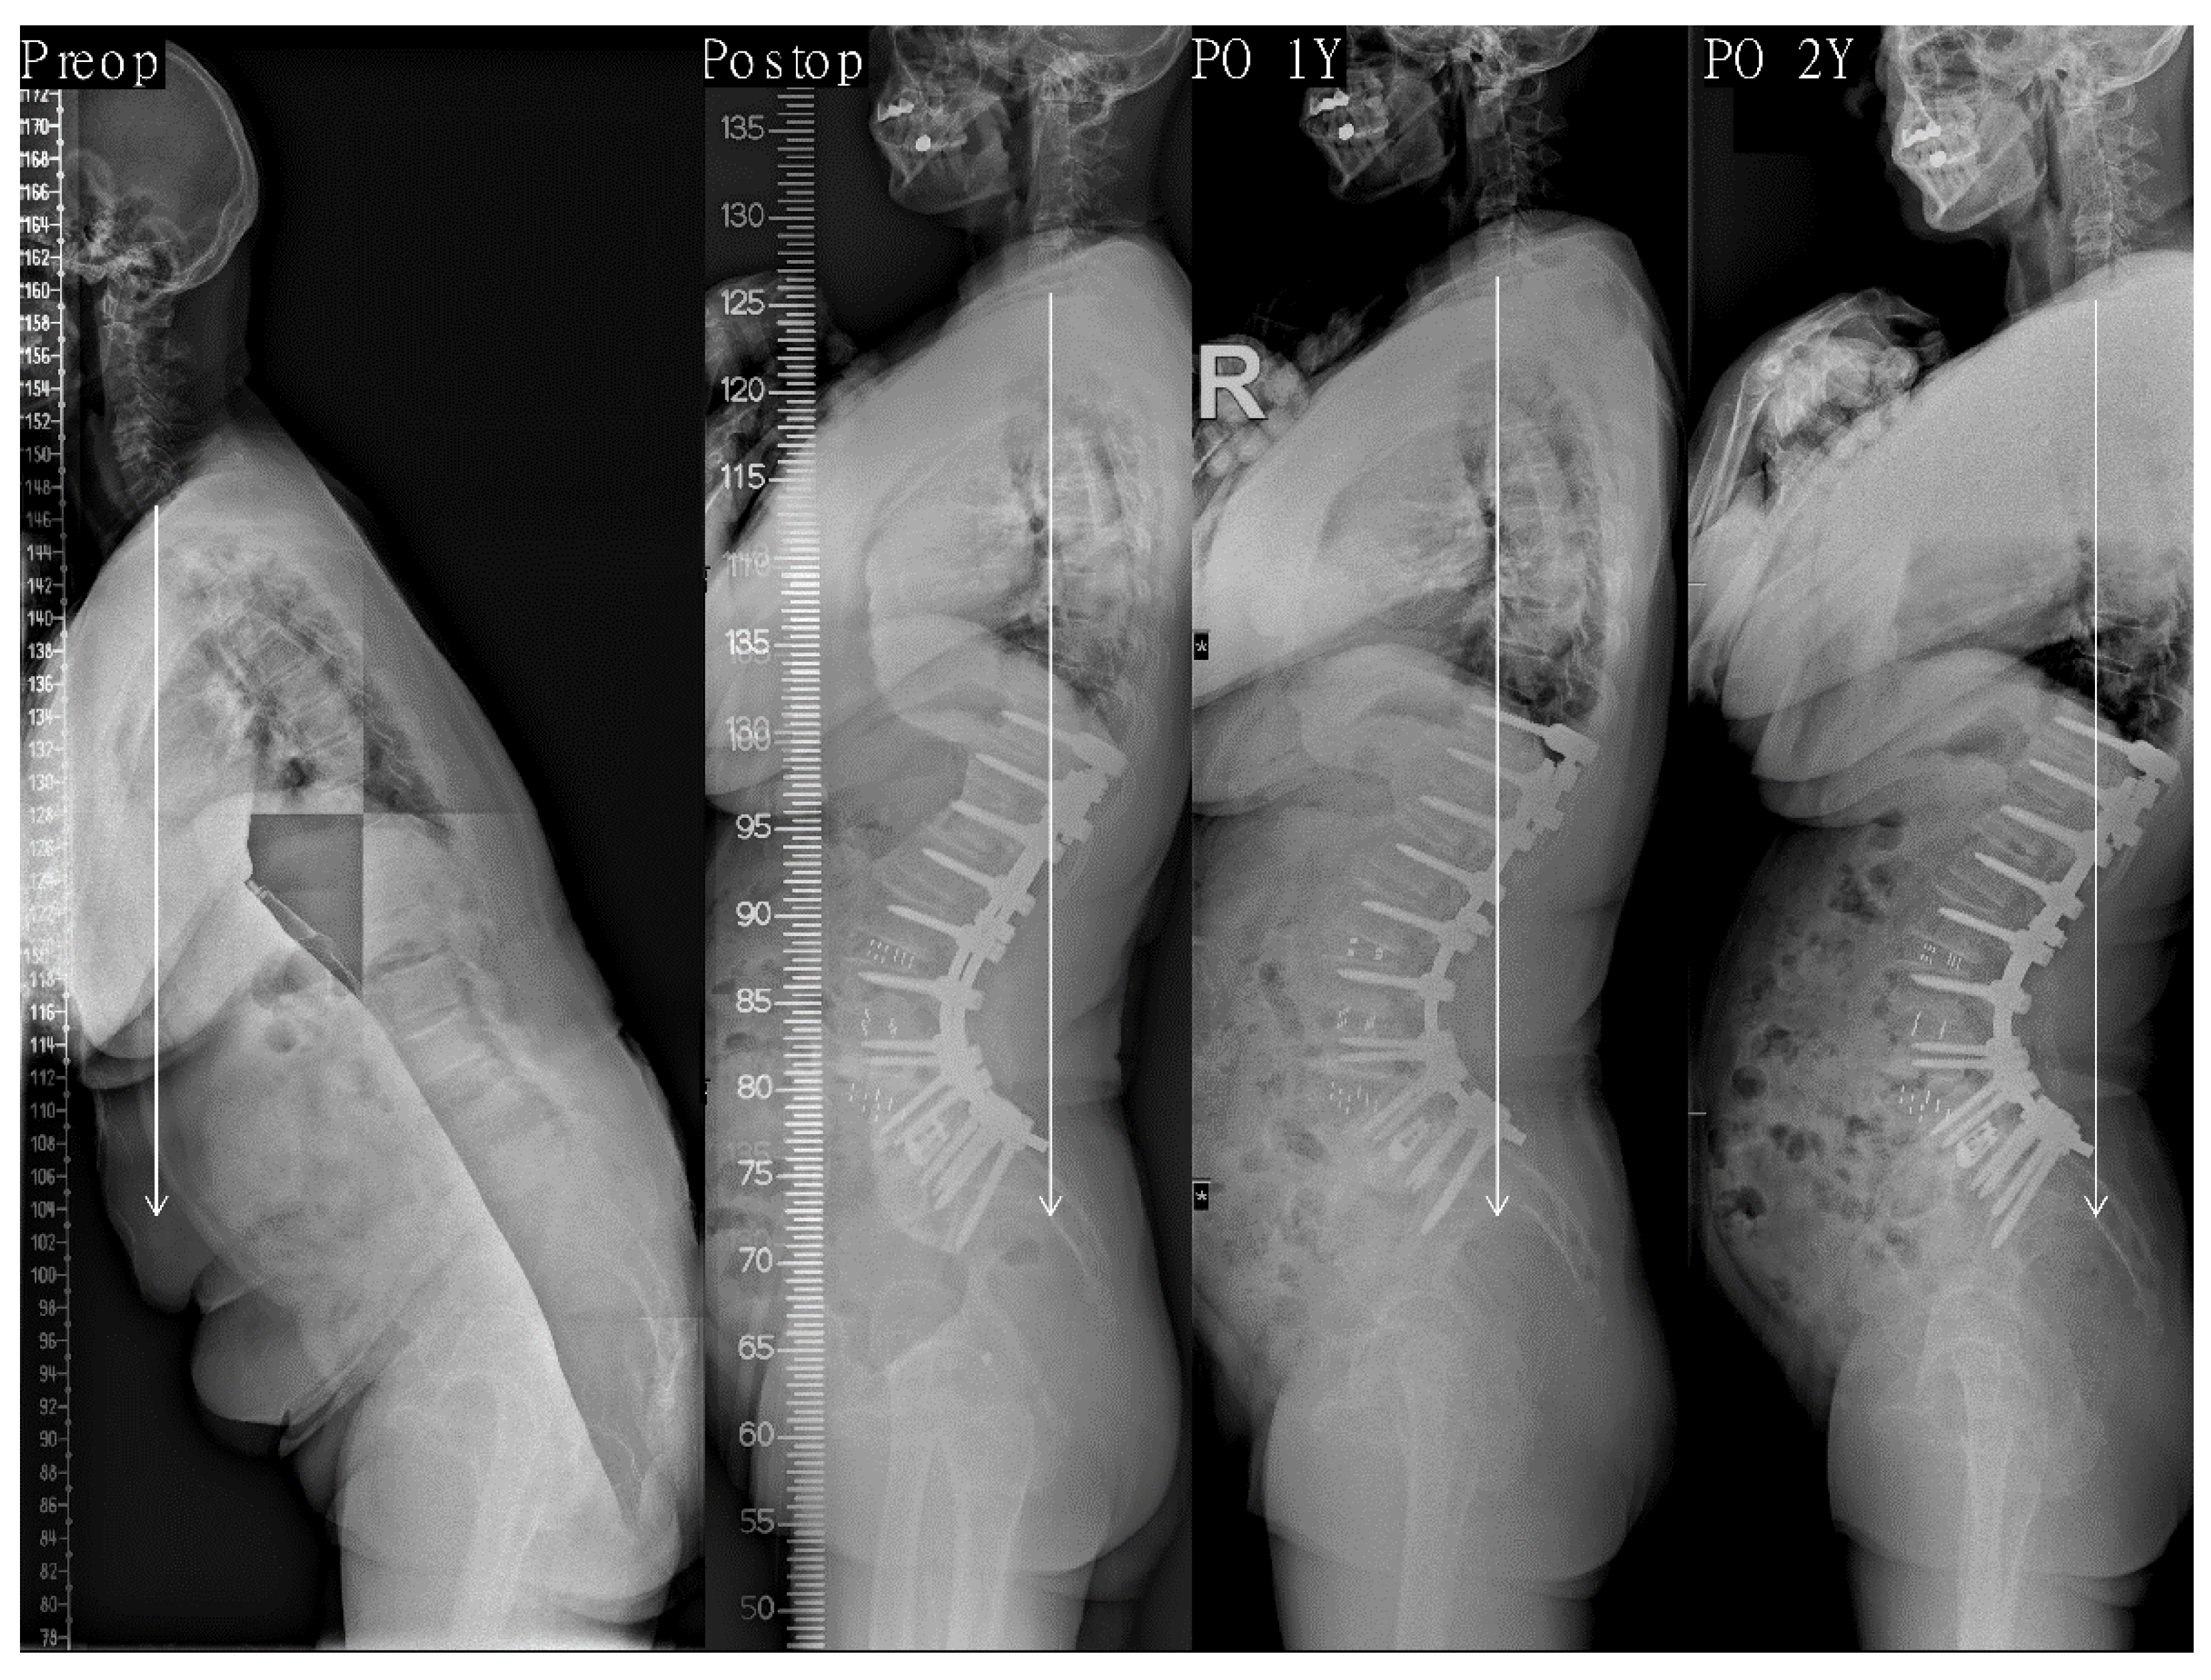

| Variables | Last Balanced Group (n = 195) | Last Non-Balanced Group (n = 33) | p-Value |

|---|---|---|---|

| SVA (mm) | |||

| Preoperative | 200 ± 65 | 193 ± 79 | 0.609 |

| Postoperative | −14 ± 26 | 0 ± 34 | 0.062 |

| Last f/u | −2 ± 27 | 70 ± 24 | <0.001 * |

| Lumbar lordosis (°) ‡ | |||

| Preoperative | 1 ± 20 | 0 ± 17 | 0.208 |

| Postoperative | −69 ± 10 | −61 ± 14 | <0.001 * |

| Last f/u | −64 ± 11 | −58 ± 18 | 0.028 * |

| PI-LL (°) | |||

| Preoperative | 57 ± 20 | 55 ± 16 | 0.643 |

| Postoperative | −13 ± 11 | −4 ± 14 | <0.001 * |

| Last f/u | −9 ± 10 | 0 ± 14 | 0.001 * |

| Pelvic tilt (°) | |||

| Preoperative | 30 ± 13 | 30 ± 16 | 0.907 |

| Postoperative | 9 ± 10 | 13 ± 9 | <0.001 * |

| Last f/u | 13 ± 10 | 22 ± 8 | <0.001 * |